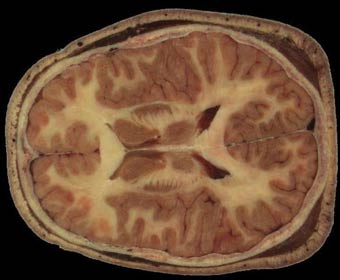

科学家找到患精神分裂症的原因(图)

美国伊利诺伊大学科学家成功发现患精神分裂症的原因,他们指出, reelin蛋白分泌不足是患者大脑中的主要损伤,reelin蛋白的功能目前尚不清楚。现在科学家认为,reelin蛋白分泌不足会使大脑中新细胞的迁移和发育受阻。负责这项研究的基米诺布·苏加亚教授指出,神经干细胞是大脑各种细胞的前身,在周围环境未知因素的影响下,神经干细胞会迁移到大脑不同部位,在那里开始生成神经细胞和神经胶质(大脑支持细胞)。

在研究过程中曾选取了两组实验鼠,在所有实验鼠的脑室中都移植有神经干细胞,其中一组实验鼠不分泌reelin蛋白。科学家发现,在正常实验鼠大脑中移植的神经干细胞迁移到海马回(大脑两半球的一个脑回)、嗅觉中枢和大脑两半球皮层,并形成“成熟”细胞。而在不分泌reelin蛋白的有缺陷实验鼠大脑中,神经干细胞会直接“消失”。另一名合作研究者埃尔米尼奥·科斯塔曾进行过研究精神分裂症死者大脑中reelin蛋白水平的实验,他发现这些死者大脑中的reelin蛋白数量降低